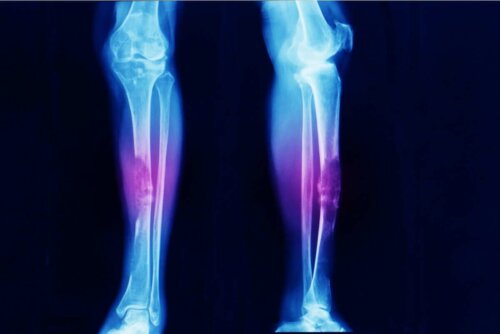

- Osteosarkomer er, som navnet indikerer, kræft i knoglerne.

Sarkomer er ikke gængse. Adskillige studier indikerer faktisk, at osteosarkomer (en svulst i knogler) kun repræsenterer 0,2% af alle ondartede tilfælde af kræft. Det betyder, der er en forekomst på omkring tre tilfælde for hver million mennesker om året.